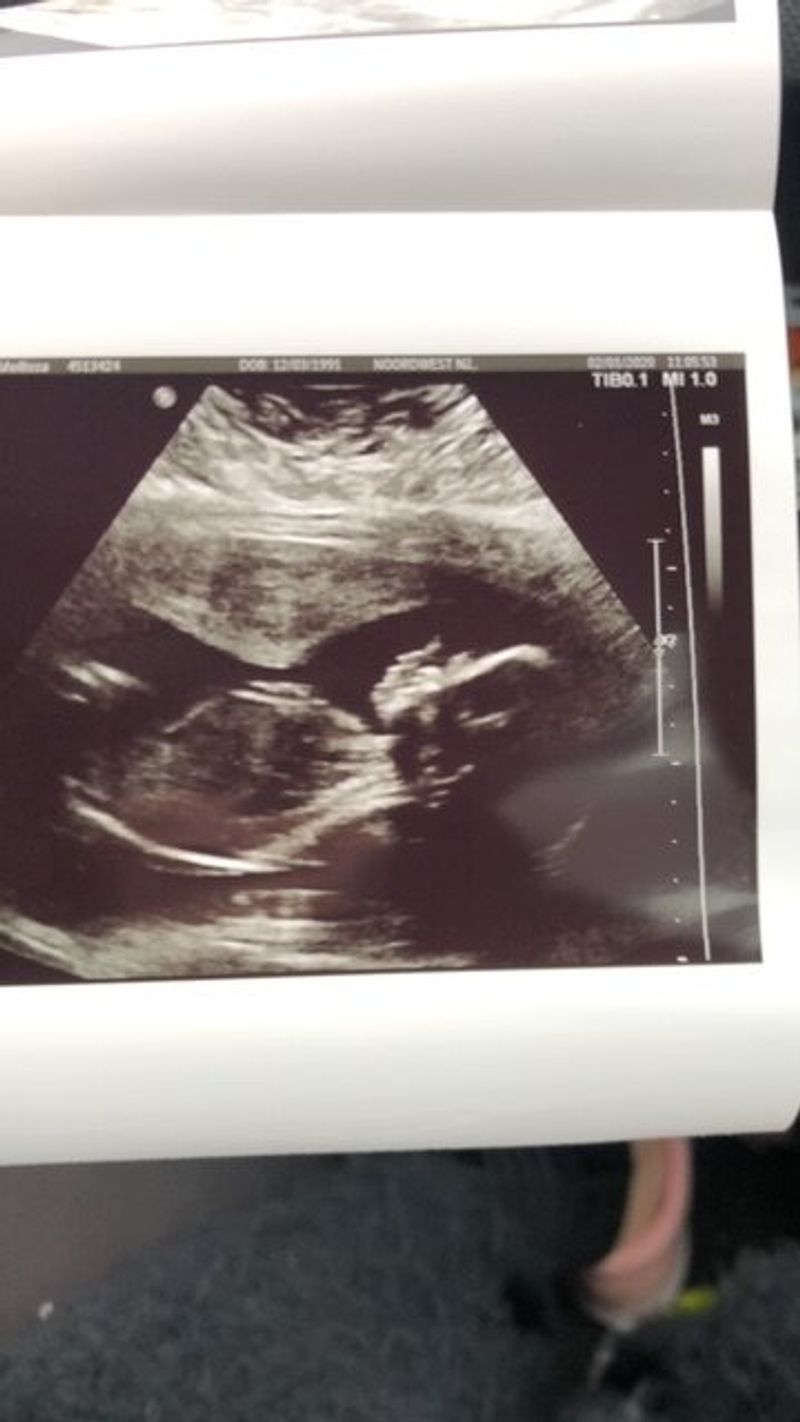

Bij 24 weken lijkt onze zoon achter liggen in zijn groei

De zwangerschap gaat tot op zekere hoogte prima. Door mijn reuma heb ik wel een afspraak bij de gynaecoloog en de reumatoloog. Ik mag zo nodig andere medicijnen gebruiken, maar mag gewoon het traject behouden via de verloskundige. Fijn. Alle echo’s en controles gaan goed, we krijgen een zoon. Meneer lijkt prima te groeien en lijkt zelfs aan de grote kant. Hij groeit keurig op P85. Ik krijg door medicatie gebruik wel extra echo’s. Bij de extra echo rond de 24 weken ziet de verloskundige een afbuigende groei, P15. Nog geen stress, het kan zijn dat de meting afwijkt omdat het kindje wat vreemd ligt. Toch word ik doorgestuurd naar de gynaecoloog, waar ik dezelfde dag nog terecht kan.

Het is helaas corona tijd en daardoor moet ik alleen naar de afspraak. Hier baal ik van, maar het is niet anders. De gynaecoloog constateert inderdaad een afbuigende groei. Vanaf dan word ik medisch en moet ik minstens eens per week naar het ziekenhuis voor een CTG, groei echo en kijken ze of de doorbloeding van de placenta nog goed is. Doordat ons zoontje klein wordt geschat, wordt er besloten dat ik ingeleid wordt met 38 weken.